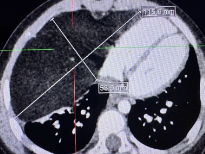

1.5厘米小孔的精准手术,首儿所胸部及肿瘤外科为8岁女孩卸下胰腺重担

8岁,本应是奔跑嬉闹、无忧无虑的年纪。可对于女孩小沐(化名)来说,过去一年多的时光,却被胰腺病灶蒙上阴霾,一家人四处辗转求医,只为给孩子寻求最稳妥的治疗方案。 一次意外外伤后的检查,开启了小沐的求医之路。在北京一家医院,小沐接受了腹部超声检查,查出胰腺体尾部有约2厘米占位性包块。胰腺位于腹腔深部...